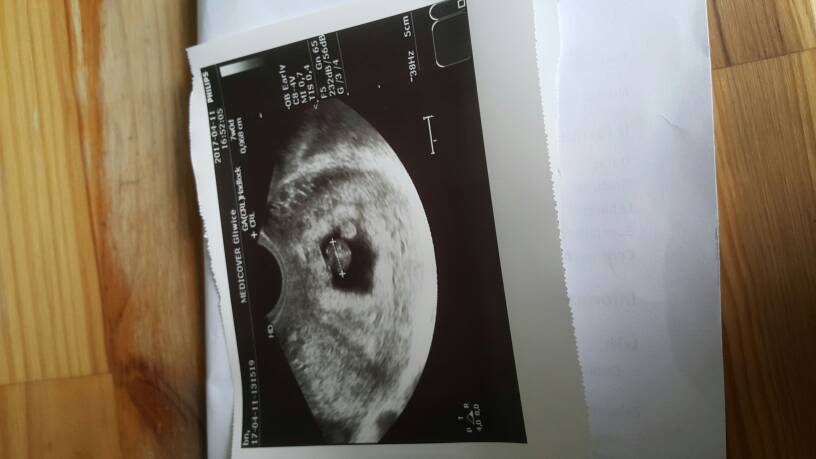

Jestem przeszczesliwa!!Jestem w ciazy!!!Biło pieknie serduszko a pecherzyk sie zaokragli♡ Roznica 2 dni wedlug usg szok!!Matko jaka jestem happy!!!!:*****Poplakalam sie tam:))[

IMG-20170411-WA0001.jpeg

Jestem przeszczesliwa!!Jestem w ciazy!!!Biło pieknie serduszko a pecherzyk sie zaokragli♡ Roznica 2 dni wedlug usg szok!!Matko jaka jestem happy!!!!:*****Poplakalam sie tam:))[Zobacz załącznik 802335